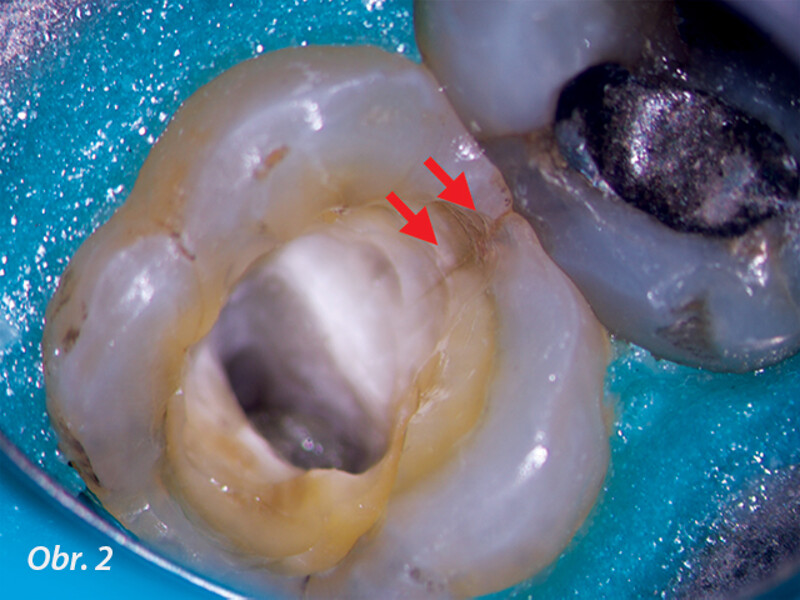

Dentální operační mikroskop v endodoncii